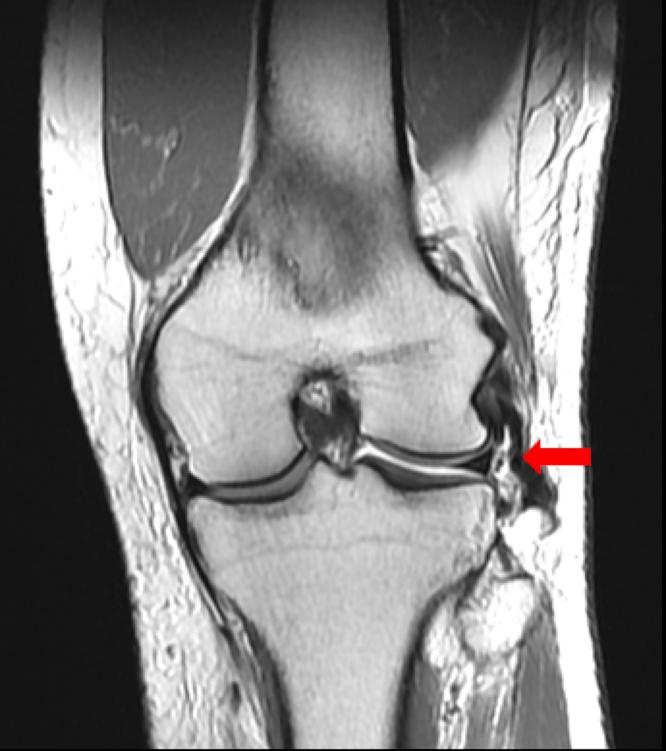

Injuries to the lateral collateral ligament (LCL) most commonly occur with concomitant cruciate ligament tears. Over the past decade, there has been increased interest in anatomic reconstruction of the posterolateral corner (PLC). Not much attention has been paid to anatomic primary LCL repair given the historically high failure rates of primary repair of lateral sided knee ligaments, but better outcomes can now be expected because of recent developments in additional suture augmentation. The purpose of this Technical Note is to describe the surgical technique of primary distal LCL repair using suture augmentation. Using this procedure, the native ligament is preserved while allowing early mobilization as suture augmentation is protective of the repaired ligament.

外侧副韧带(LCL)损伤最常伴有交叉韧带撕裂。在过去十年中,人们对后外侧角(PLC)的解剖重建越来越感兴趣。鉴于历史上外侧膝关节韧带一期修复的失败率较高,一期LCL解剖修复并未得到太多关注,但由于近期在额外缝线增强方面的进展,现在可以期待更好的结果。本技术说明的目的是描述使用缝线增强进行LCL远端一期修复的手术技术。采用该手术方法,可保留天然韧带,同时由于缝线增强对修复韧带具有保护作用,可实现早期活动。